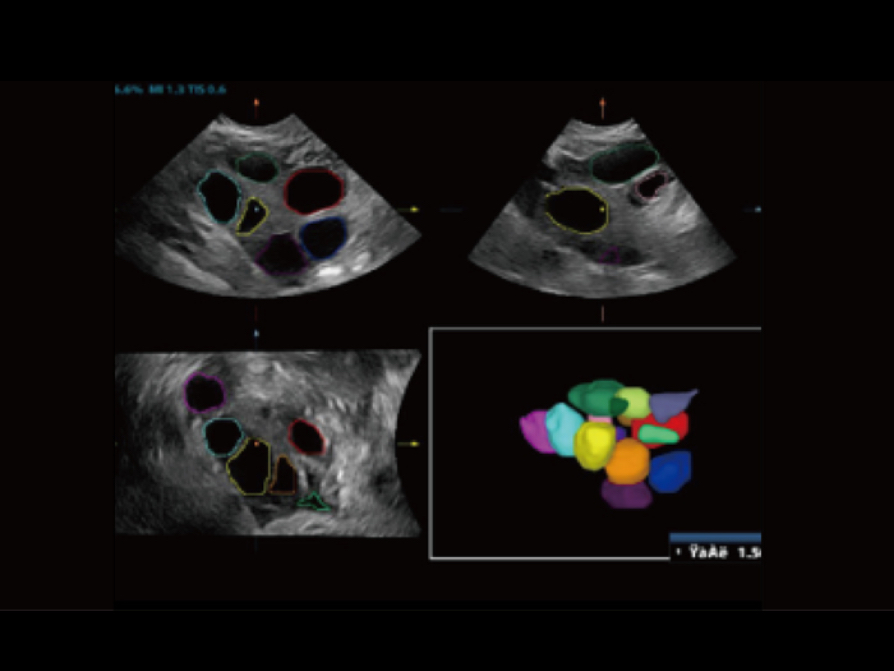

Smart FLC automatically detects the number of follicles and calculates each volume from a 3D ovarian volume image, assuring accurate assessment of follicles, essential for IVF exams.